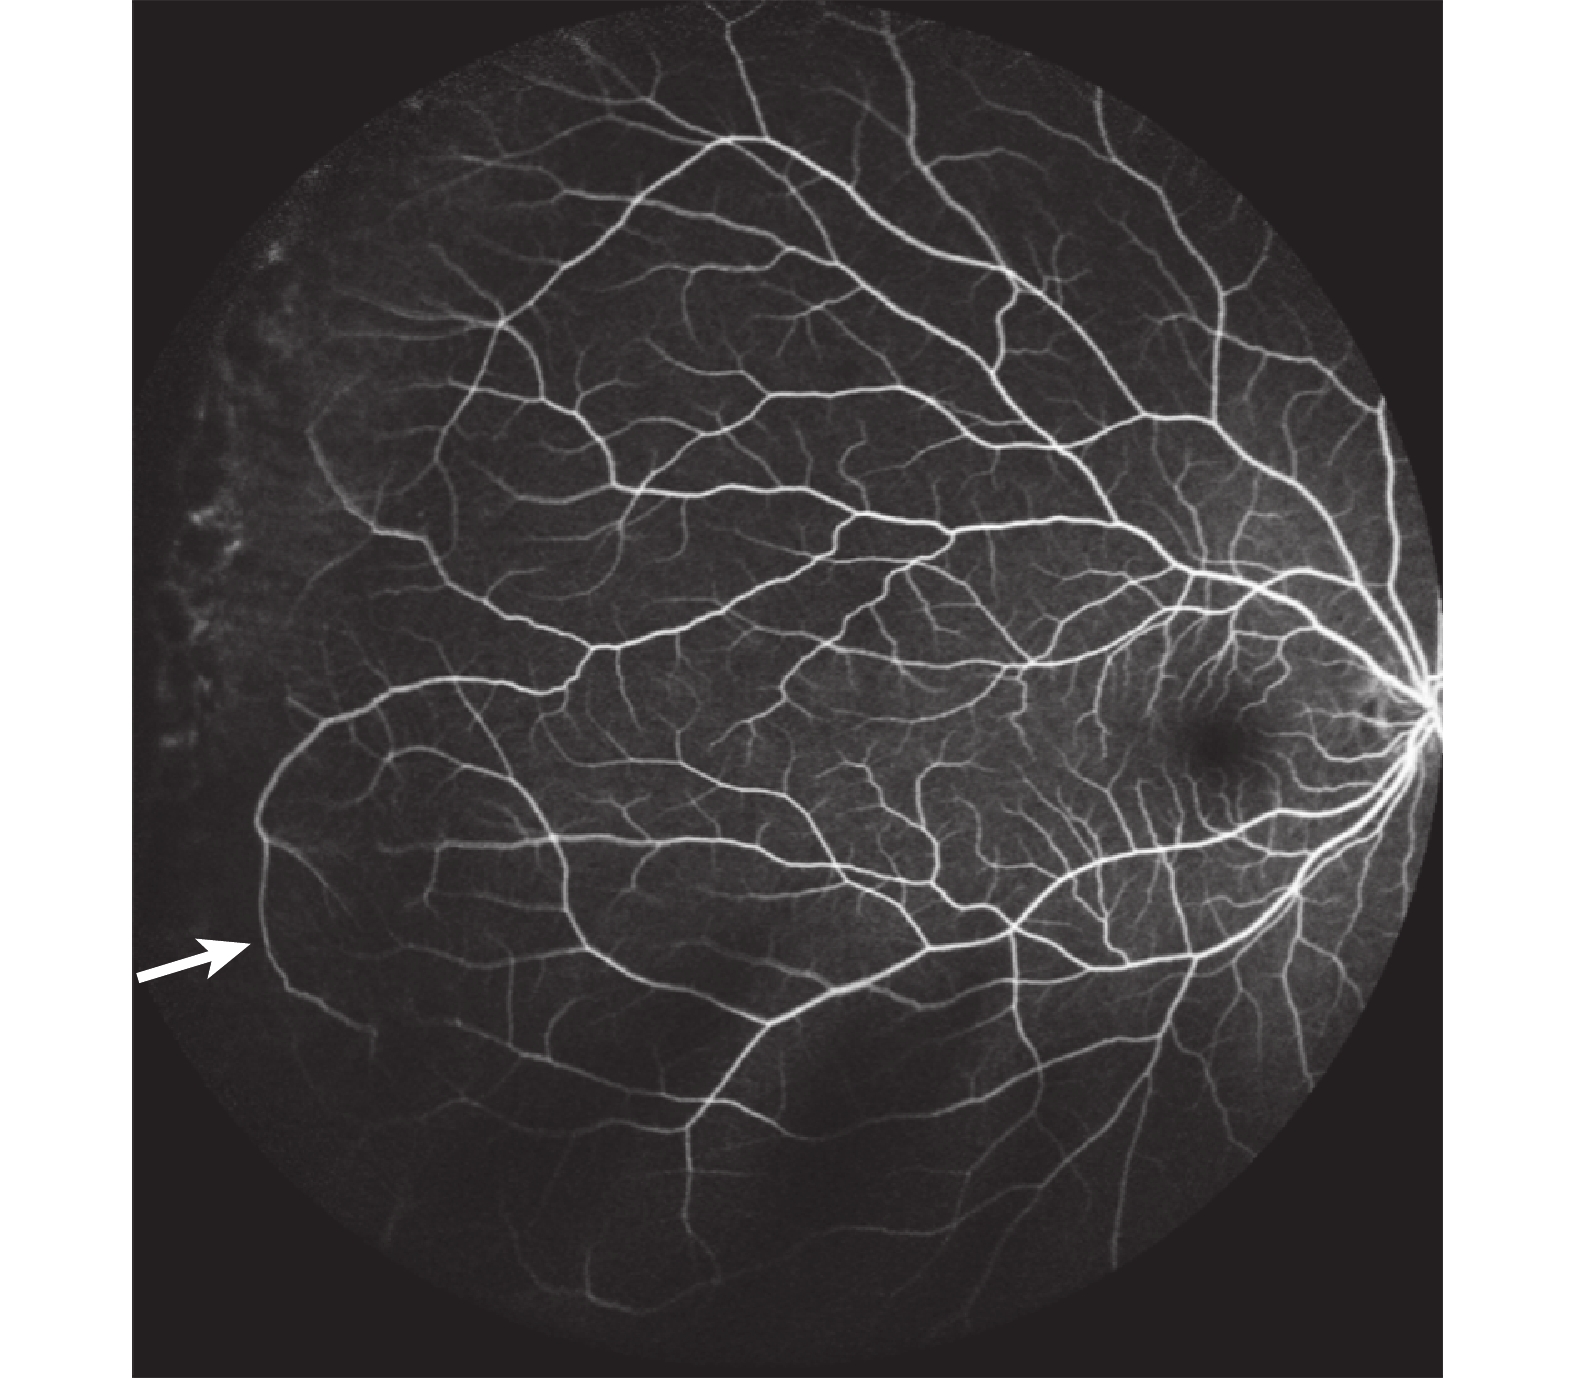

圖2

患兒母親眼底造影

周邊部分血管迂回生長(白箭)